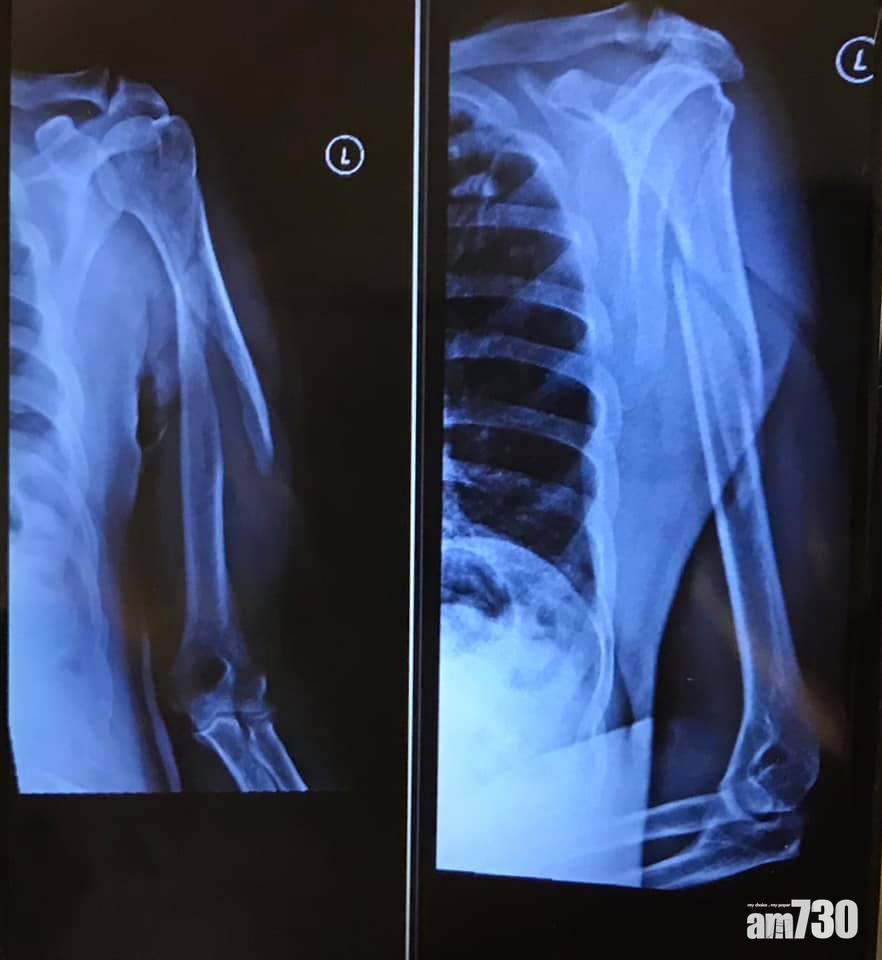

熱血公民運頭塘社區主任黃兆健在社交網站表示,當時有市民被打傷,送院檢查後,證實手臂骨折需要留院治理。

黃兆健在社交網站指有市民被打傷,手臂骨折需要留院治理。(黃兆健@FB)